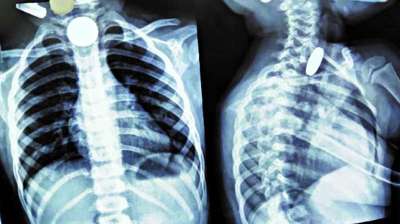

खिलौना नहीं सिक्का था! बच्चे ने निगले 5-10 रुपये के सिक्के, डॉक्टरों ने ऑपरेशन कर निकाले

24 Jul, 2025 04:09 PM IST | MP1NEWS.COM

दिल्ली : दिल्ली के एक सरकारी अस्पताल के डॉक्टरों ने 12 वर्षीय बच्चे की जान बचाई है। बच्चे ने पांच और दस रुपये के तीन सिक्के निगल लिए थे। सिक्के...